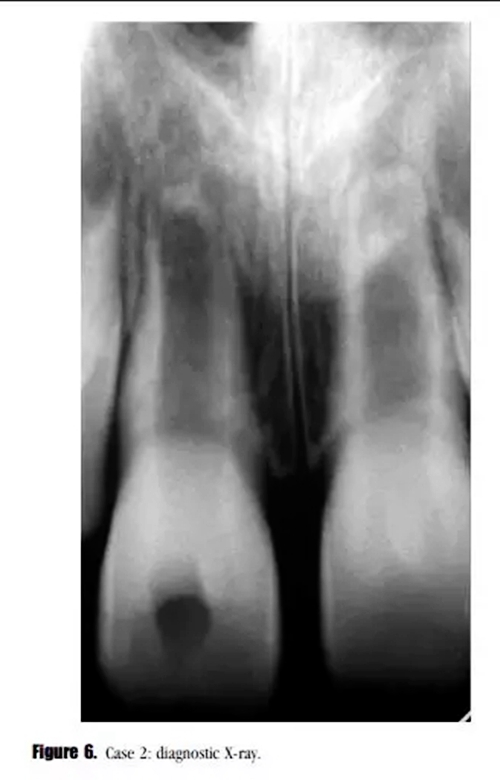

主訴:右上頜恒切牙區(qū)口腔前庭區(qū)腫脹。(圖6)。

專科檢查:牙齒輕微松動(dòng),可見開髓孔。叩診輕微不適,牙周探診深度在正常范圍內(nèi)。黏膜上可見一竇道。

輔助檢查:診斷X線示,牙根發(fā)育處于第4階段,未見明顯的根尖周透射影像,雙側(cè)中切牙根尖區(qū)可見阻射影像。21牙髓電活力測(cè)試結(jié)果正常。11診斷為:急性根尖周炎。